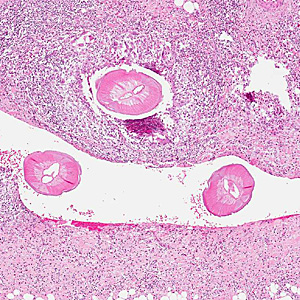

A 55-year-old woman sought medical attention for a nodule on the right side of her head. The patient presented with pain on the right side of her head for the past two months. Two weeks prior to seeking medical attention, she felt a painful 0.5 cm lump on her right temple. The nodule was removed surgically and sent to Pathology for histological testing. Stool and blood specimens were also collected, processed, and examined for parasites with negative results. The nodule was sectioned, stained with hematoxylin and eosin (H&E), and examined microscopically. Images were captured and sent to DPDx for diagnostic assistance. Figure A was captured at 40x; Figure B at 100x; Figures C and D at 200x magnification. What is your diagnosis? Based on what criteria?

Figure A